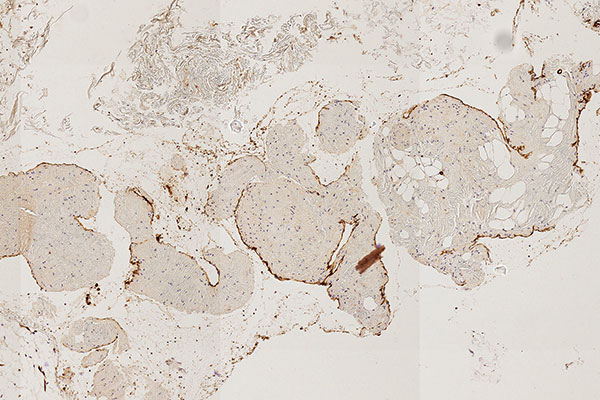

Histopathologischer Schnitt; CD31-Färbung zur spezifischen Anfärbung von Gefäßendothelzellen, die dann dunkelbraun gefärbt sind. 80-fache Vergrößerung des Stanzzylinders. Damit ist bewiesen, dass die äußere zelluläre Begrenzung der sichtbaren Läsion Blutgefäßendothelien entspricht.

Durch immunhistochemische Färbung mit CD31 (Blutgefäßendothel), das die Läsion auskleidet, und den irregulären, zum Teil lückenhaft asymmetrischen Besatz mit glatten Muskelzellen (SMA-Färbung) sowie der Nachweis von atypischen verteilten Kollagen- und elastischen Fasern (EvG-Färbung) in der venenartigen Gefäßwand machen die Diagnose hochwahrscheinlich. Venöse Malformationen zeigen kaum Proliferationsaktivität (MIB-1).